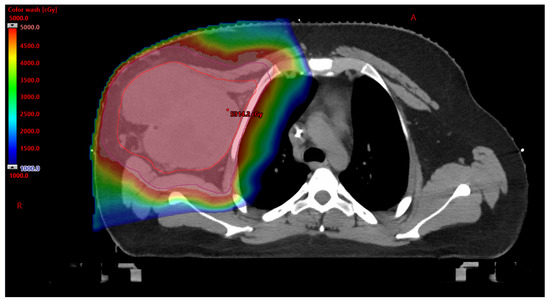

3.2.1. Benefits to PBT